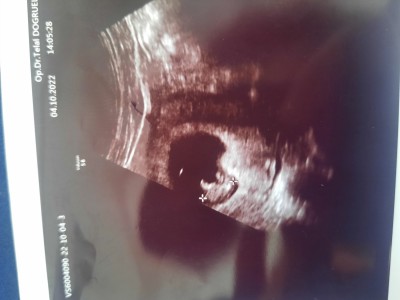

Kizlar keseye gore cinsiyet tahmininde bulunur musunuz

image

Benim kesemde böyleydi kızım oldu <3

Kaç haftalık bu minnoş yaa daha küçücük bişey

9 haftalık canım:)